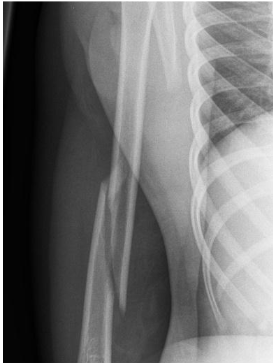

Spiral Humeral fracture

Spiral fractures often occur from a twisting mechanism, while transverse fractures to the humerus typically occur with direct blow to the arm.